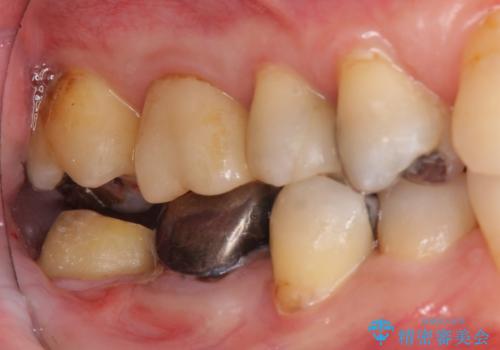

⑷最終形成、歯型とり

⑸クラウン装着

- 19万円(右下7 仮歯1万円、PGAクラウン 8万円、歯周外科手術(APF)10万円)費用は治療当時の料金となります

そうすることで、正確に歯型もとれ、精密なクラウンが製作でき、再度虫歯になる可能性を低くできます。